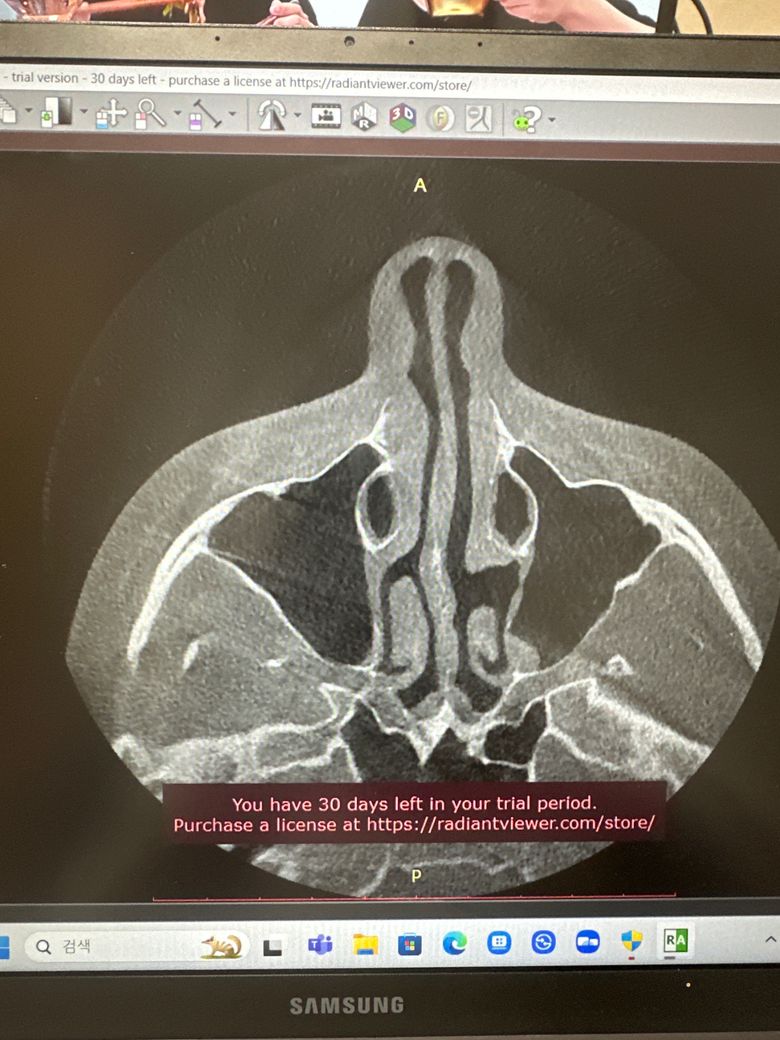

코 ct사진인데 분석 부탁드립니다!

질문 그대로 입니다 이비인후과에서 ct찍은 사진인데 ct상으로 보이는것들이랑 문제가 있다면 말씀해주시면 감사하겠습니다ㅠ

• 2번 째 사진

올리신 사진 두 컷 가지고 구체적이고 자세한 평가가 가능하지는 않습니다만, 올리신 사진 두 컷 속에는 특별히 이상 소견이 있어 보이거나 하지 않습니다.